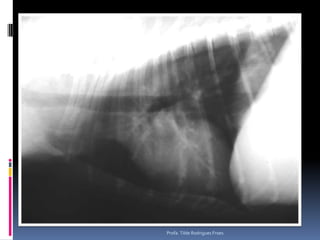

Animal: Mike, canino Canino, macho, 11 anos, ROTTHX: Claudicação posteriores    Déficit de propriocepçãoProfa. Tilde Rodrigues Froes

Animal: Mike, caninoCanino, macho, 11 anos, ROTTHX: Claudicação posteriores Déficit de propriocepçãoProfa. Tilde Rodrigues Froes